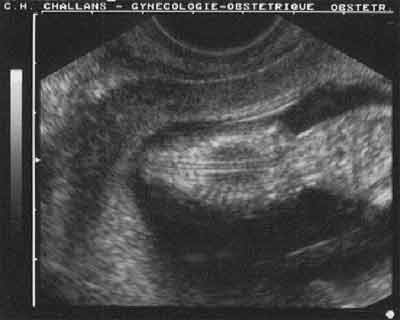

Coupe frontale